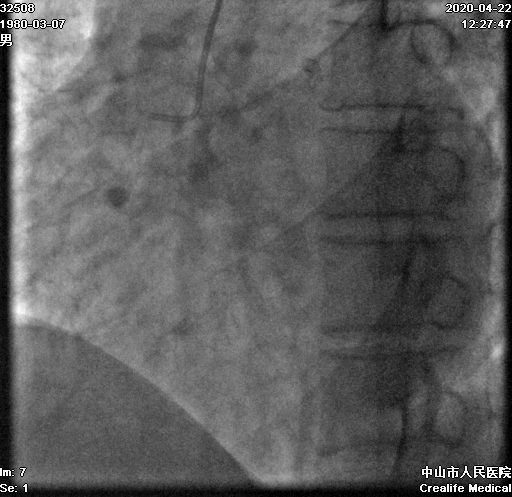

术前冠脉造影:

1.RCA CTO正逆向策略如何制定和实施?

2.逆向通路的选择及如何通过?